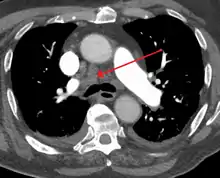

| Widened mediastinum | |

|---|---|

| Other names | Mediastinal widening |

![]() | |

| Widened mediastinum in a patient with achalasia | |

Widened mediastinum/mediastinal widening is where the mediastinum has a width greater than 6 cm on an upright PA chest X-ray or 8 cm on supine AP chest film.[11]

A widened mediastinum can be indicative of several pathologies:[12][13]

- aortic aneurysm[14]

- aortic dissection[15]

- aortic unfolding

- aortic rupture

- hilar lymphadenopathy

- anthrax inhalation - a widened mediastinum was found in 7 of the first 10 victims infected by anthrax (Bacillus anthracis) in 2001.[16]

- esophageal rupture - presents usually with pneumomediastinum and pleural effusion. It is diagnosed with water-soluble swallowed contrast.

- mediastinal mass

- mediastinitis

- cardiac tamponade[17]

- pericardial effusion

- thoracic vertebrae fractures in trauma patients.